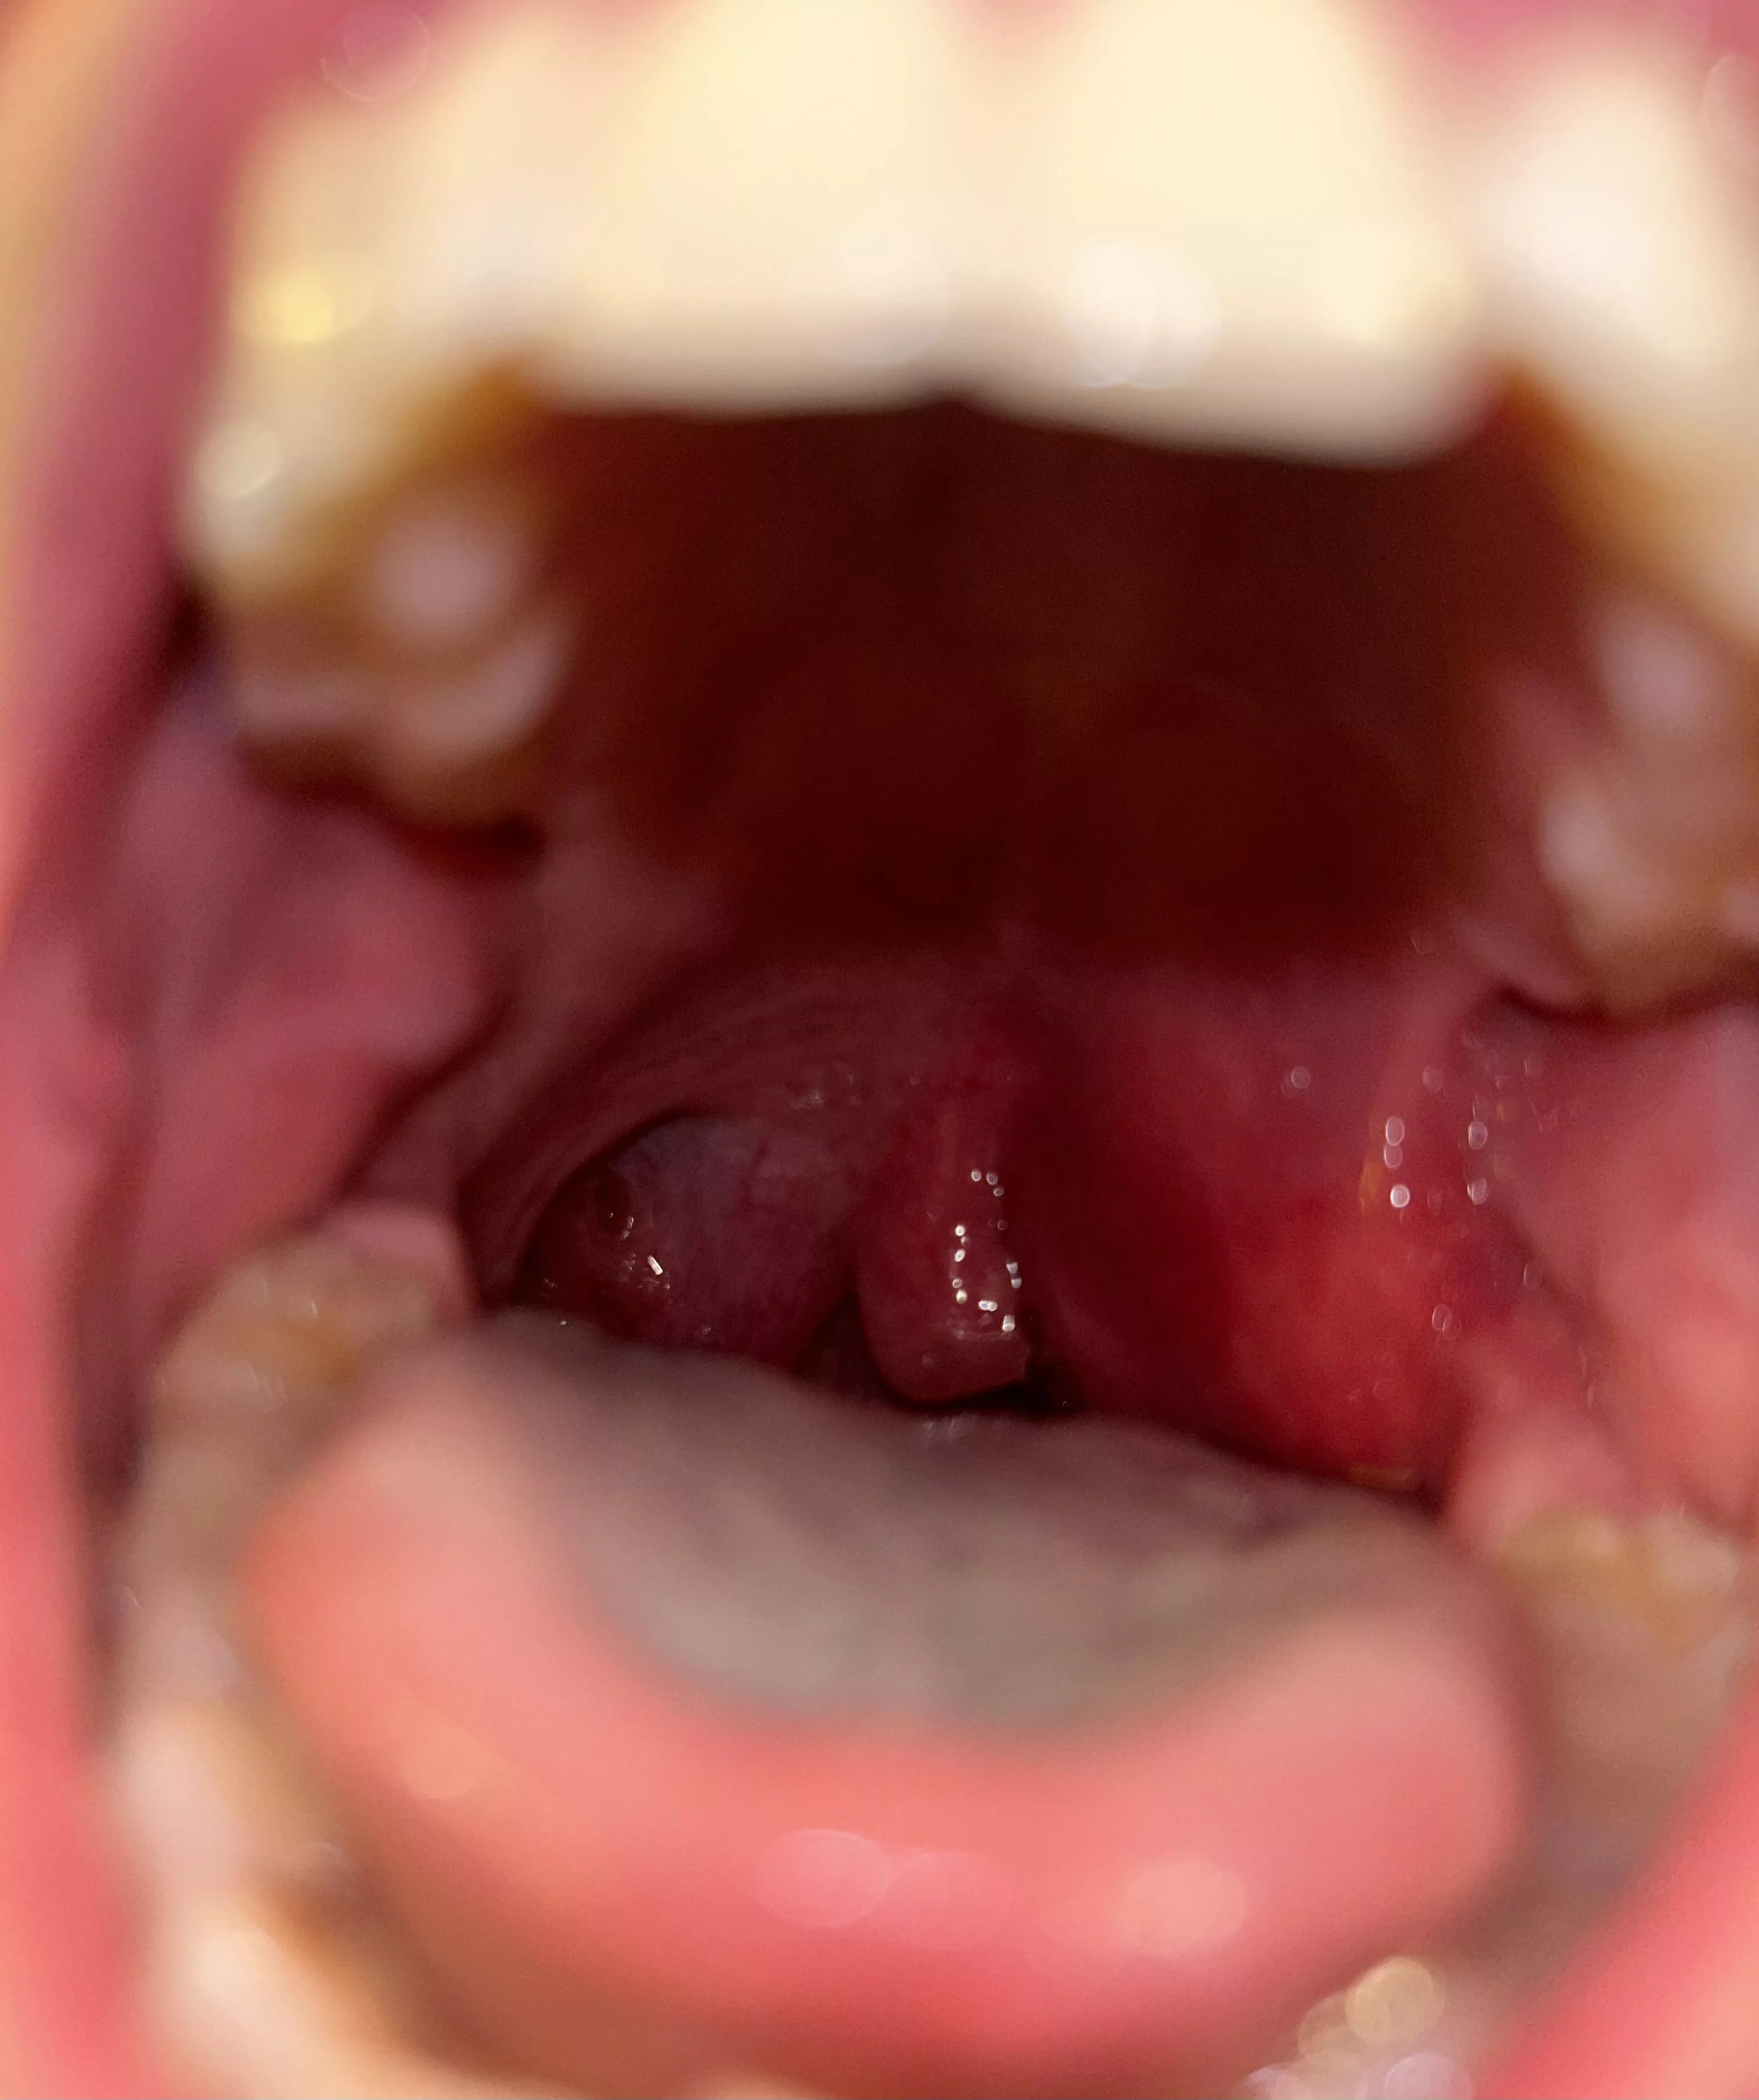

Quinsy before it burst at home. Extremely painful and scary.

Quinsy before it burst at home. Extremely painful and scary. posted by Minute_Tomatillo_399 Previous Next